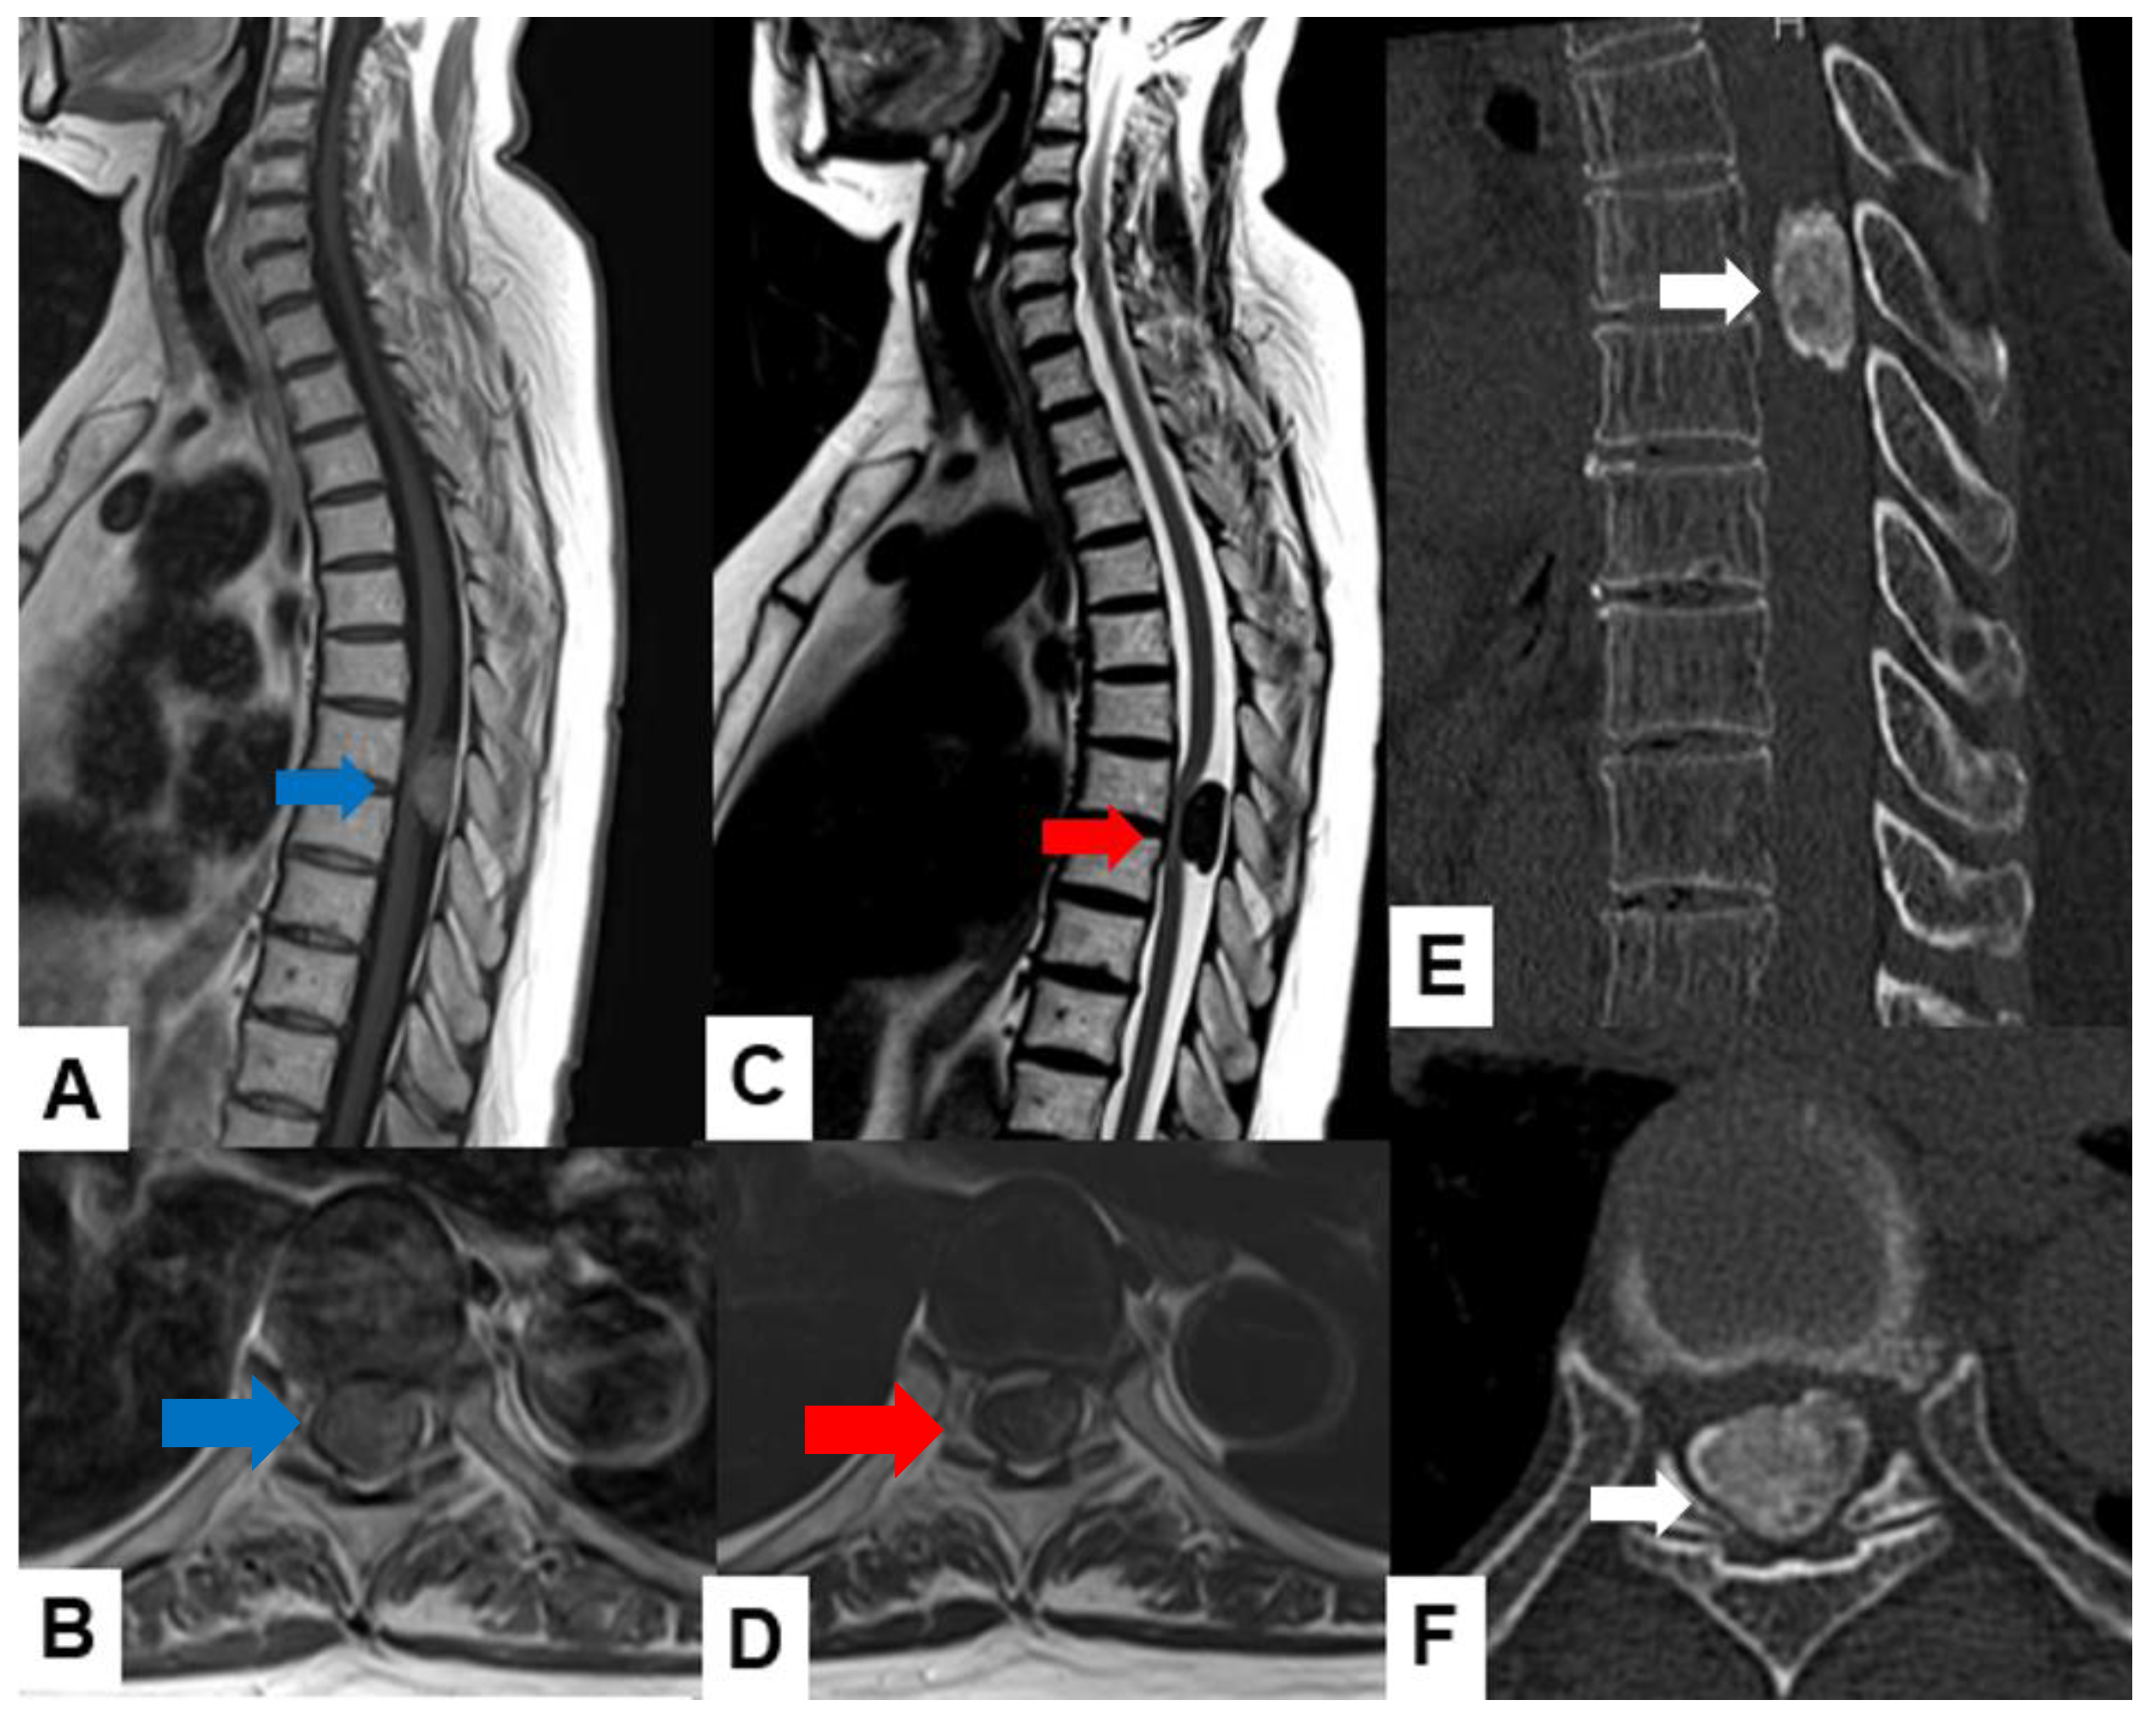

Astrocytoma: Pilocytic astrocytomas usually indicate well-circumscribed intramedullary masses with cystic lesions. These tumors exhibit a mixed signal intensity in both T1-weighted and T2-weighted images (Figure 5). High-grade astrocytomas, such as glioblastomas, present as infiltrative growth, with ill-defined margins and heterogeneous enhancement. These tumors may indicate surrounding edema.

Figure 5.

Fourteen M, spinal astrocytoma, grade 3. (A) T1-weighted midsagittal image, (B) T2-weighted midsagittal image, and (C) enhanced T1-weighted midsagittal image. Red arrows indicate tumor and blue arrow shows tumor enhancement.

Ependymoma: Myxopapillary ependymomas typically present as well-defined intradural extramedullary masses with a heterogeneous signal intensity in T1-weighted images and hyperintensity in T2-weighted images (Figure 6). These tumors often demonstrate avid contrast enhancement.

Figure 6.

Thirty-seven M, spinal ependymoma, grade 1. (A) T1-weighted midsagittal image, (B) T1-weighted axial image at C4/5, (C) T2-weighted midsagittal image, (D) T2-weighted axial image at C4/5, (E) enhanced T1-weighted midsagittal image, and (F) enhanced T1-weighted axial image at C4/5. Red arrows indicate tumor; blue arrow shows enhancement. Green arrows indicate large syringomyelia.